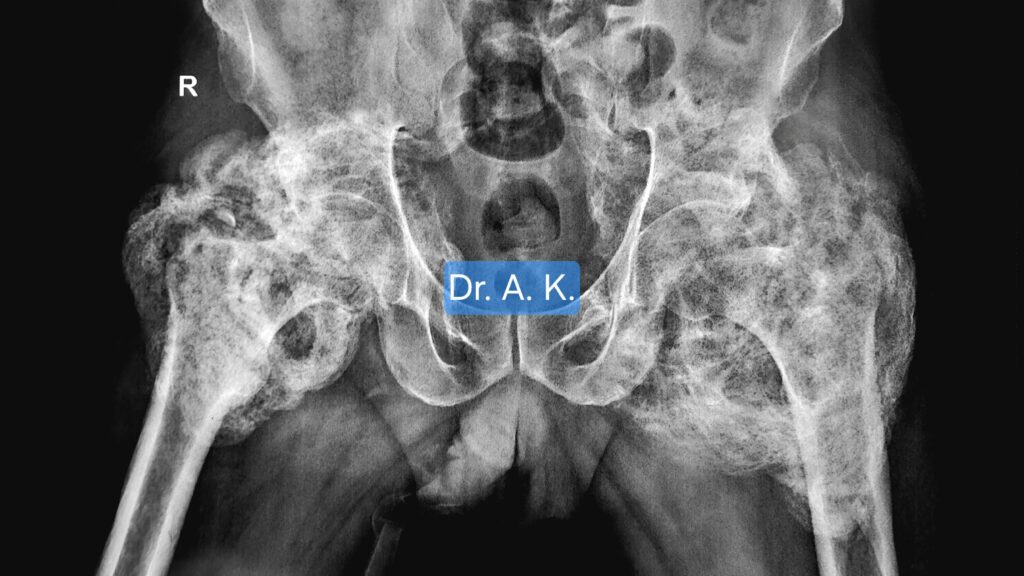

🧩 How We Diagnose a Stiff Hip

At our Indore Hip Clinic, diagnosis starts with:

- X-rays and 3D CT scans 🖼️ to locate the bony bridges

- MRI to see muscle involvement

- Functional assessment — how much the joint can move

- Blood tests to check bone activity (alkaline phosphatase, calcium)

This helps us plan whether total hip replacement is possible — and what special steps we’ll take during surgery.